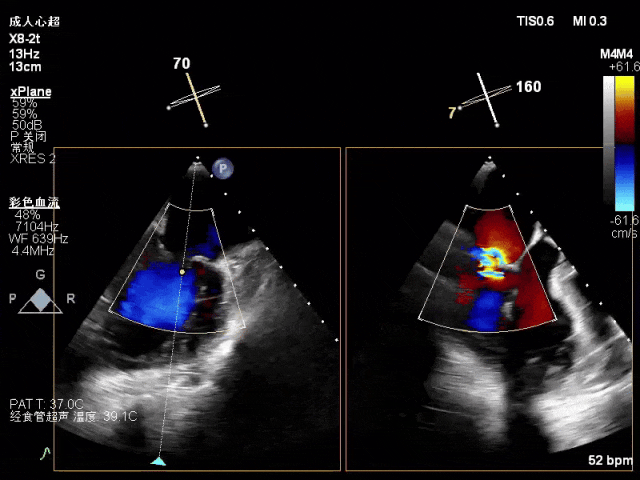

术中超声(关键步骤)

混合性MR,P2脱垂连枷(脱垂范围15mm,连枷间距4mm),腱索断裂

新分型:ACA型,反流2区及两侧,MR 4+,VC:3×14mm

A2:24mm,P2:17mm,AP:38mm,MVA约5.7cm²